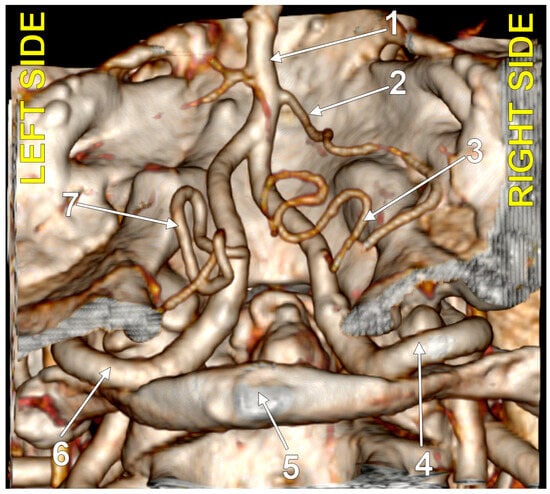

4.1. Typical PICA

4.3. Extradural Origin of the PICA

4.4. Transdural Origin of the PICA

4.7. The Bihemispheric PICA

4.8. The Caudal Loop of the PICA